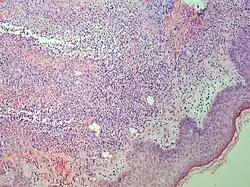

Prevesicular stage of bullous pemphigoid Image at right shows influx of inflammatory cells including eosinophils and neutrophils in the dermis (solid arrow) and blister cavity (dashed arrows), and deposition of fibrin (asterisks).[15] However, the diagnosis of bullous pemphigoid consist of at least 2 positive results out of 3 criteria:[19]

• Pruritus and/or predominant cutaneous blisters

• Linear IgG and/or C3c deposits (in an n- serrated pattern) by direct immunofluorescence microscopy (DIF)

• Positive epidermal side staining by indirect immunofluorescence microscopy on human salt-split skin (IIF SSS) on a serum sample.